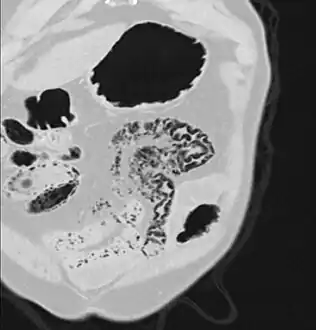

Pneumatosis intestinalis in computed tomography with intestinal ischemia. Lung window for better representation of the gas deposits in the intestinal walls.